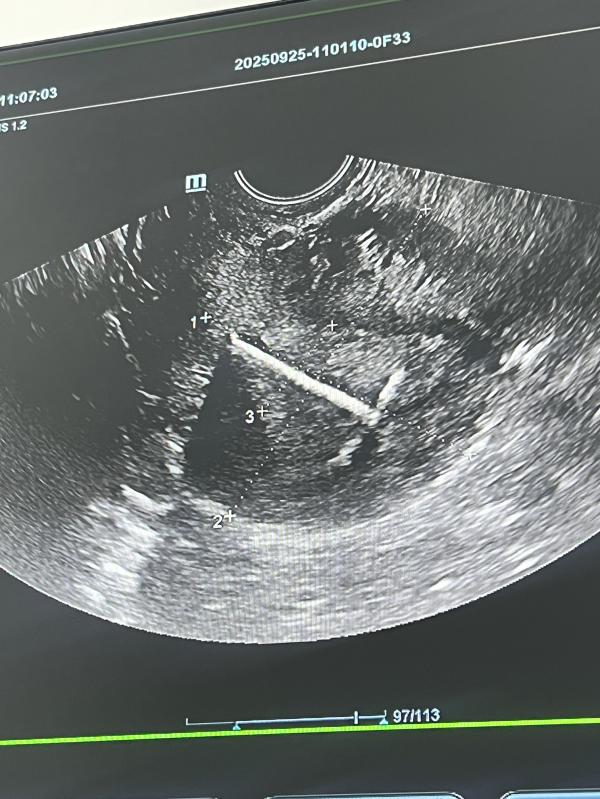

Фото моей идеальной спирали , которая стоит как надо уже на протяжении 7 лет , почему не меняла , да потому что на каждом узи ее хвалили .

Но сейчас после кд я буду ее менять и так страшно и боязно, что так идеально не поставят . 😂обычная серебряная спираль . Служила мне верой и правдой .

Я с вами, тоже не меня на протяжении 7 лет, так как стояла идеально и не беспокоила🤭

У меня тоже спираль идеально стоит